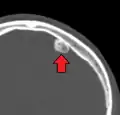

An osteoma (plural osteomas or less commonly osteomata) is a new piece of bone usually growing on another piece of bone, typically the skull. It is a benign tumor.

When the bone tumor grows on other bone it is known as "homoplastic osteoma"; when it grows on other tissue it is called "heteroplastic osteoma".[1]